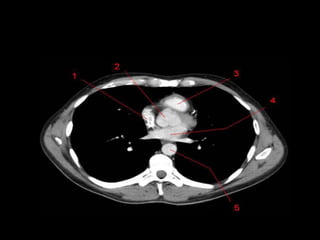

TC mediastino superior